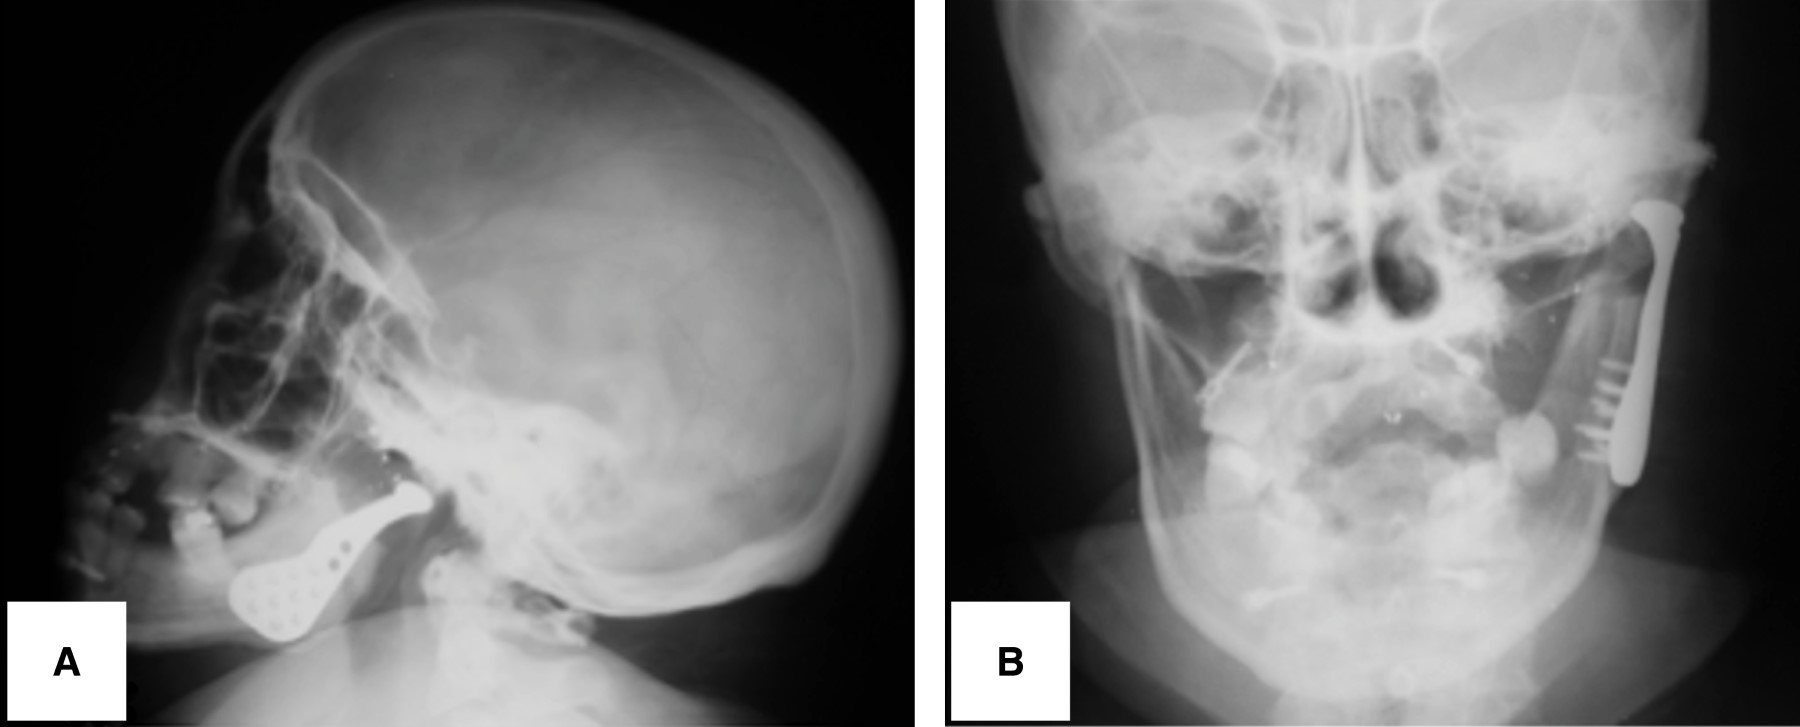

La paciente del caso 1 posterior a la cirugía presento 20 milímetros de apertura bucal, iniciando fisioterapia forzada al día siguiente del RTATM y durante seis meses más. Incluso ella refiere continuar con los mismos de manera ocasional por iniciativa propia. Actualmente con un seguimiento a cinco años no hay evidencia de reanquilosis, presentando una apertura de 35 mm (Figura 7 A y B), con movimientos mandibulares protrusivos y laterales y oclusión estable. La comparación de una corte coronal de una vista inferior del cráneo mostró simetría de las articulaciones temporomandibulares (Figura 8 A y B).

Figura 3

Figura 7

Figura 8